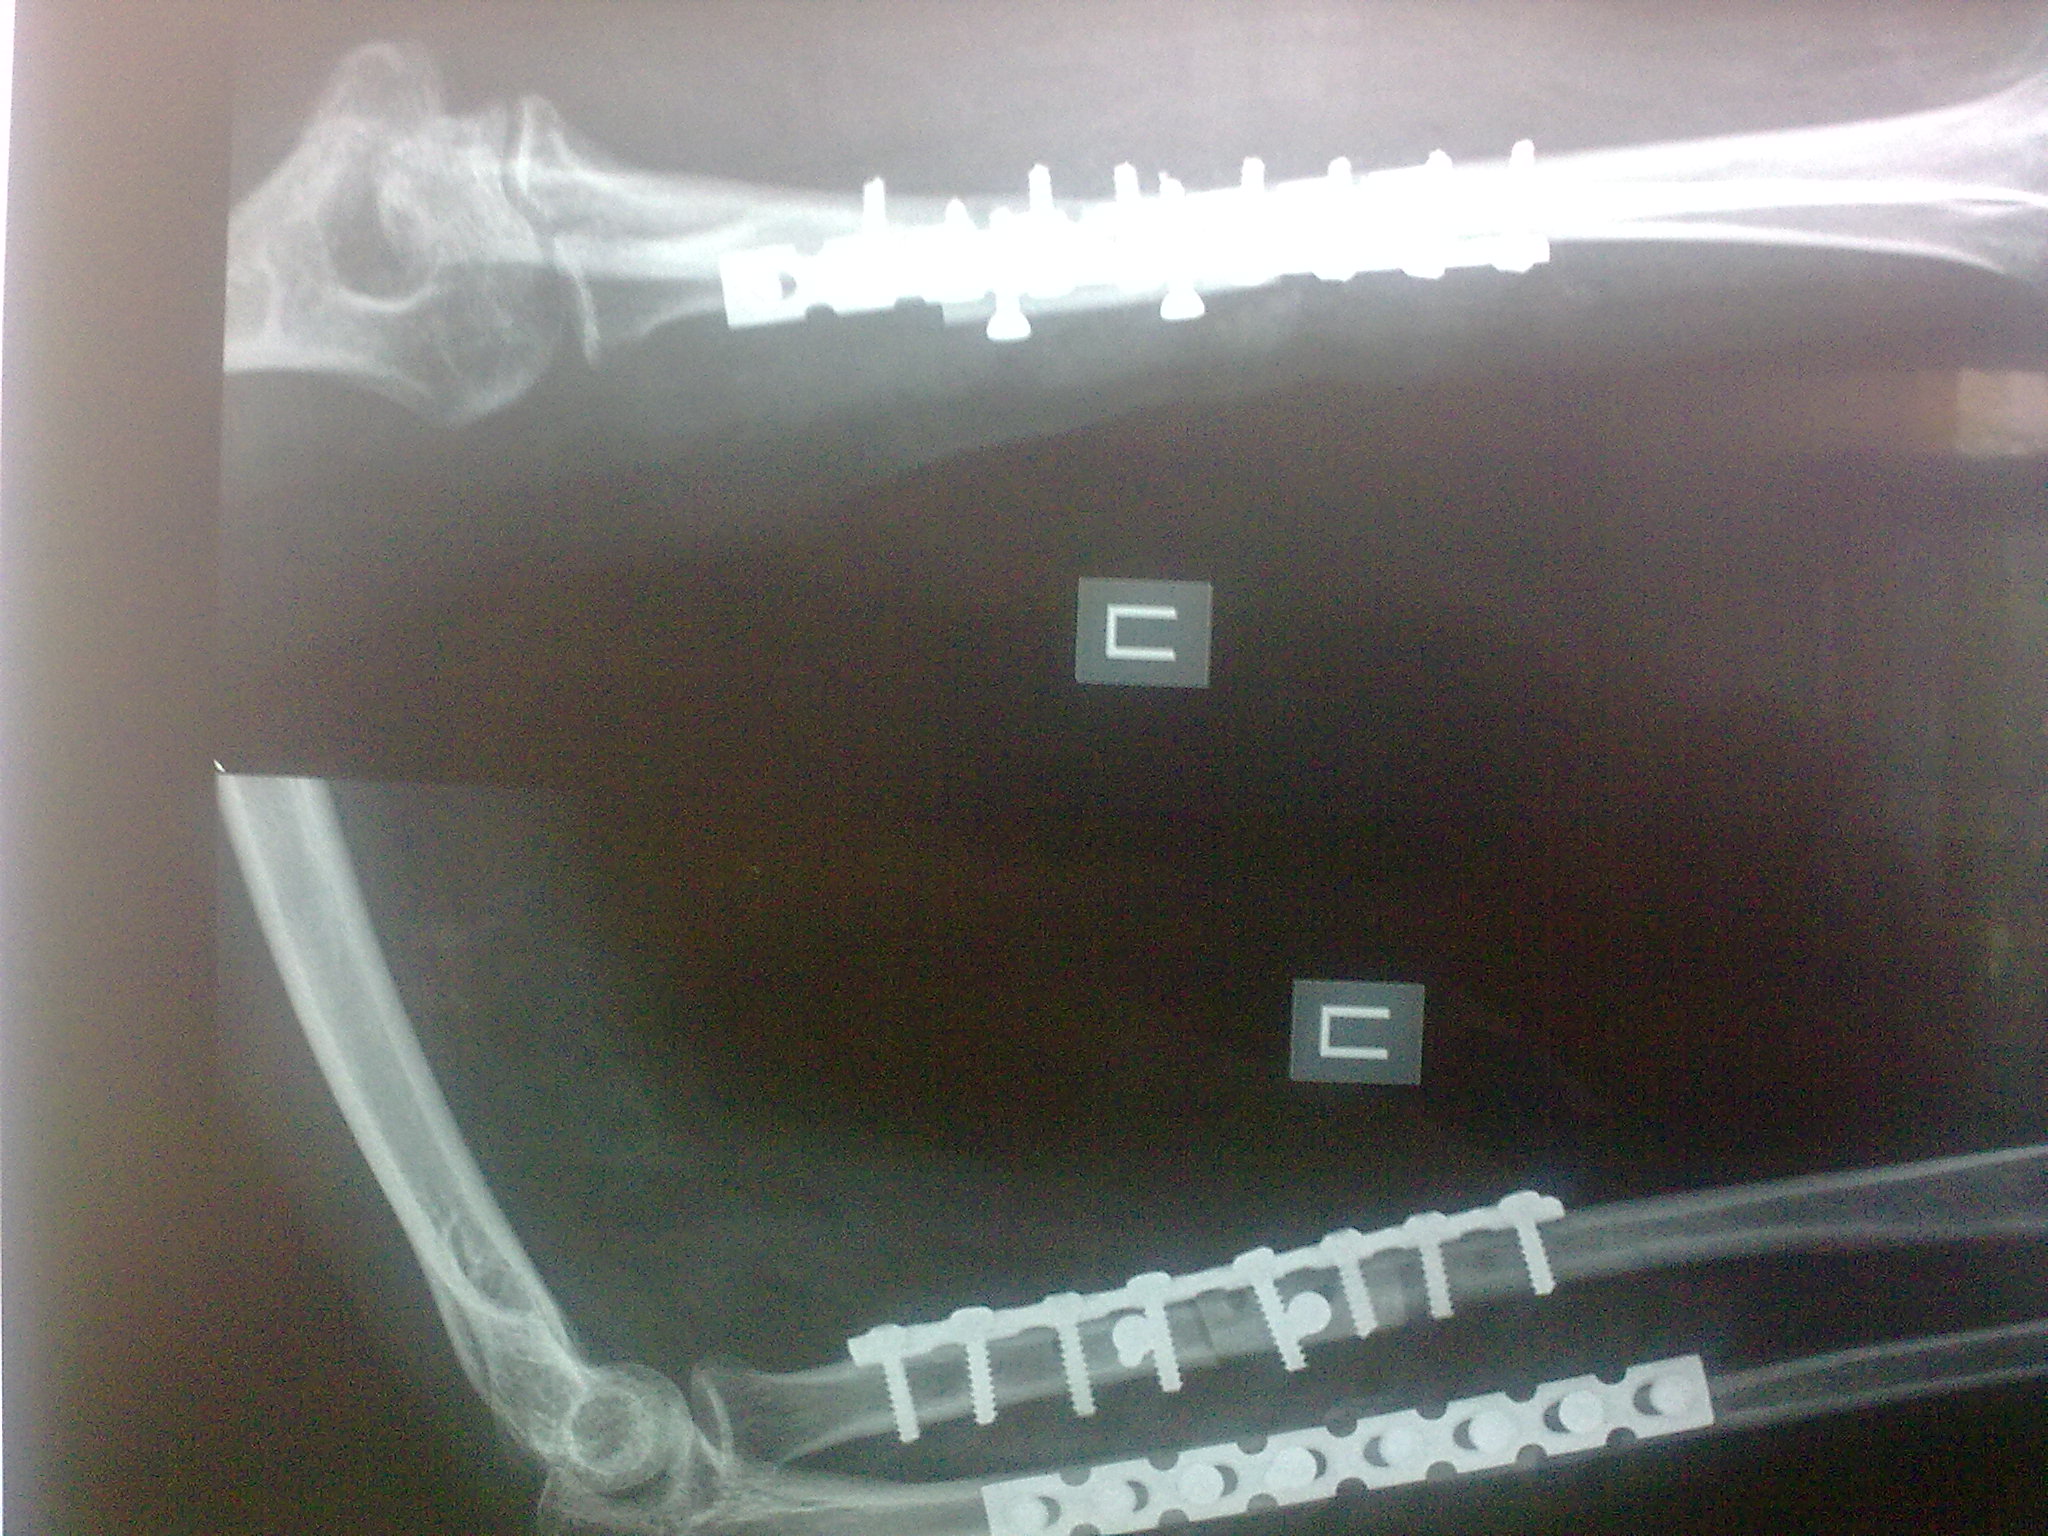

Пациентка С. 23 лет. В марте 2009 года операция остеосинтез костей предплечья пластинами по поводу оскольчатого перелома.

04.07.09. при совершении супинационных движений предплечья ощутила хруст (низкоэнергетическая травма). На рентгенограммах несросшийся перелом костей предплечья, перелом конструкций. Коллеги подскажите что делать, поделитесь опытом.

Спасибо коллеги. Выполнили ресинтез реконструкционными пластинами с костной аутопластикой кортикальными трансплантатами с декортикацией.

Кликните для загрузки файла 16072009402[1]

611KB (625938 bytes)